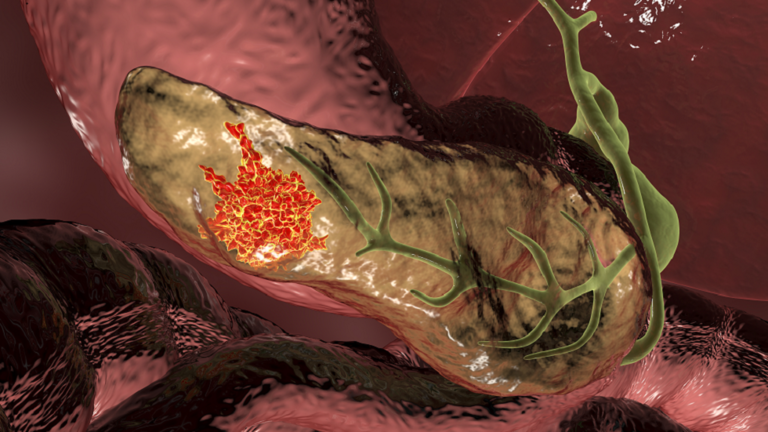

قد يتمكن الأطباء يوما ما من اكتشاف أحد أكثر السرطانات فتكا والأصعب اكتشافا من خلال تحليل البراز.

ويعيش ربع الأشخاص الذين تم تشخيص إصابتهم بسرطان البنكرياس حاليا أكثر من عام، و5% فقط يعيشون لمدة عشر سنوات.

ويعتبر سرطان البنكرياس مميتا للغاية ويرجع ذلك جزئيا إلى صعوبة اكتشافه وعلاجه.